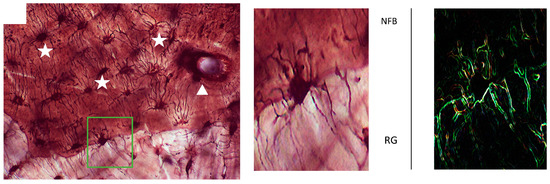

3. Results